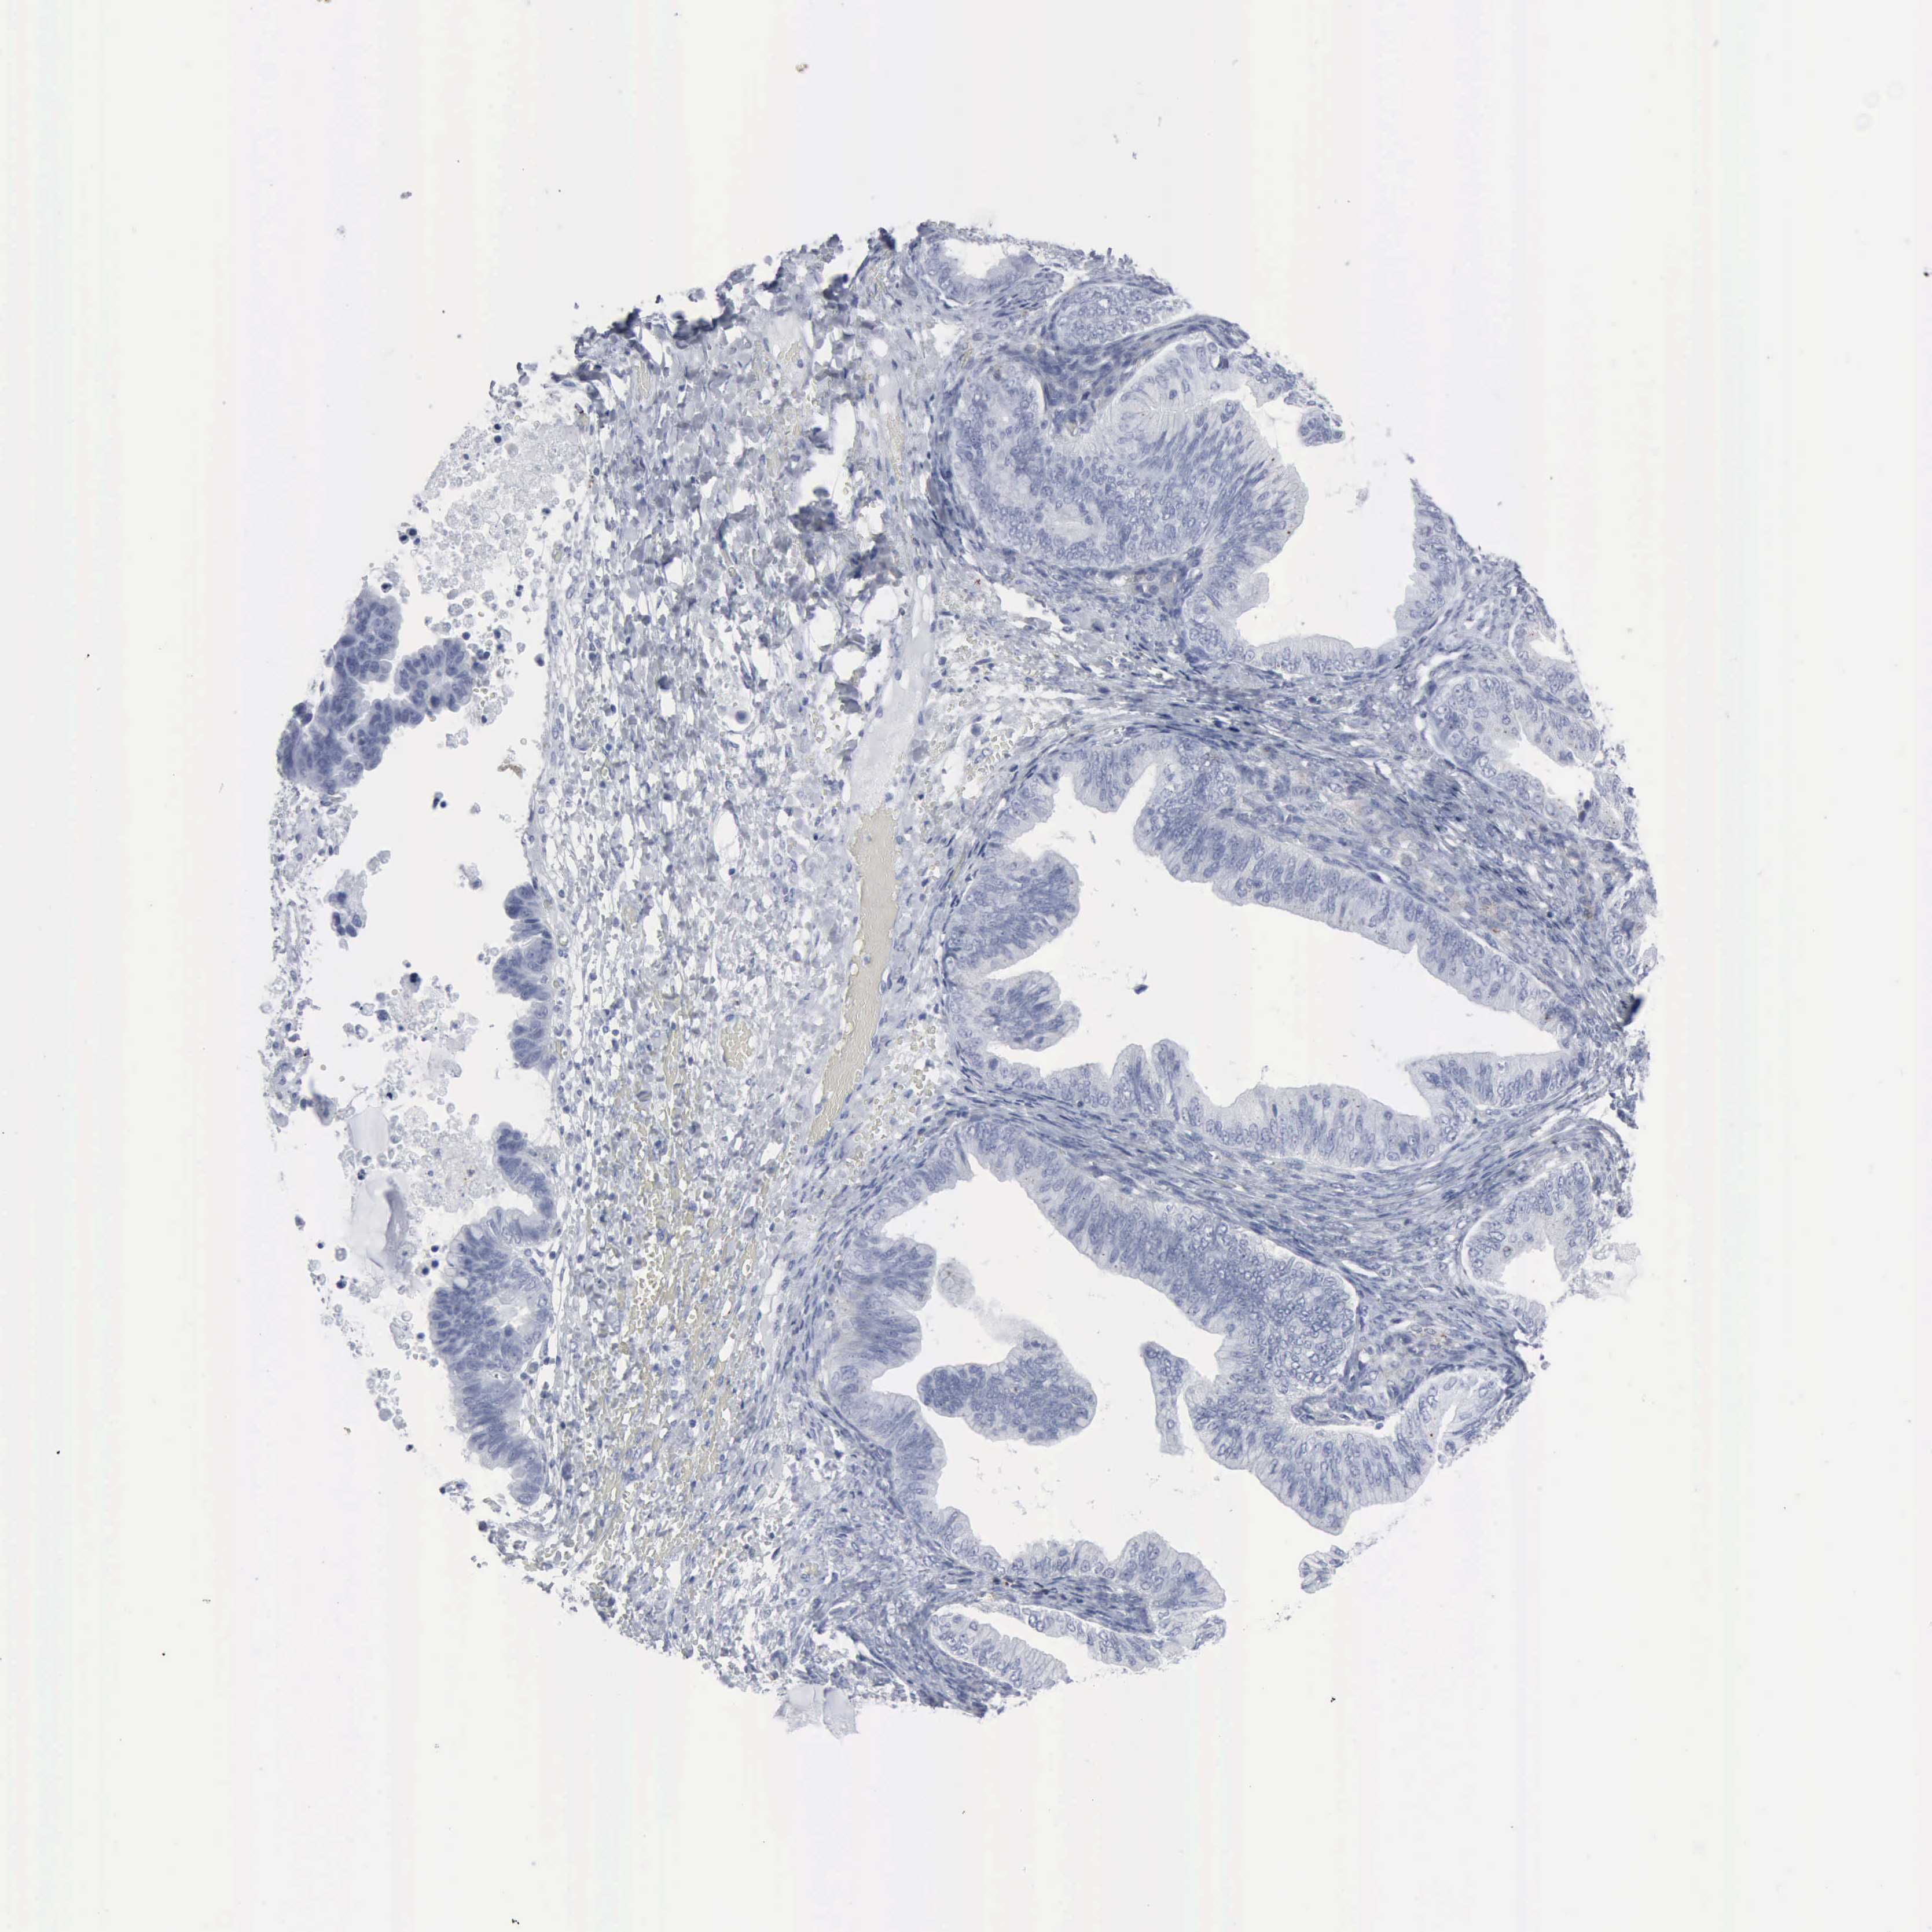

OVARIAN CANCER - Protein expressioni

A mouse-over function shows sample information and annotation data. Click on an image to view it in a full screen mode. Samples can be filtered based on level of antibody staining by selecting one or several of the following categories: high, medium, low and not detected. The assay and annotation is described here.

Note that samples used for immunohistochemistry by the Human Protein Atlas do not correspond to samples in the TCGA dataset.

Antibody stainingi

Antibody staining in the annotated cell types in the current human tissue is reported as not detected, low, medium, or high, based on conventional immunohistochemistry profiling in selected tissues. This score is based on the combination of the staining intensity and fraction of stained cells.

Each image is clickable and will lead to virtual microscopy that enables deeper exploration of all samples and also displays staining intensity scores, fraction scores and subcellular localization as well as patient and tissue information for each sample.

Antibody HPA000237

Antibody HPA000966

Cystadenocarcinoma, mucinous, NOS

Carcinoma, endometroid

Cystadenocarcinoma, serous, NOS